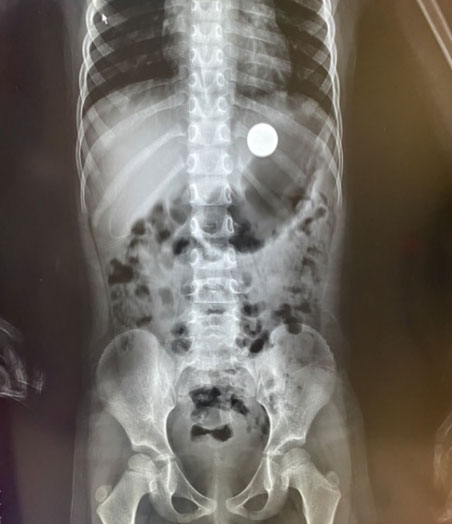

X光检查发现胃中的圆形异物

做好准备工作后,梁红亮麻利地拿起胃镜轻轻地插入小女孩的口腔,进入食管、贲门、胃体、胃窦,胃里有不少小女孩吃进去的酸奶、奶酪,阻挡着视野,一直找找翻翻,也不见硬币的踪迹。

“在胃底,和食物混在一起了”只见一枚硬币“躺”在胃底,清晰可见,“快,异物网篮”。梁红亮和李杭娟默契配合,把异物网篮插入,在胃内张开,慢慢的伸到硬币旁准备将其套进网篮中。一次、两次、三次,通过不断调整角度,慢慢将硬币全部放进异物网篮中间,再慢慢拉紧收回。梁主任用最轻的力气,缓缓地抽出胃镜,将取出的硬币放在纱布上,大家一直紧绷着的心才放了下来。